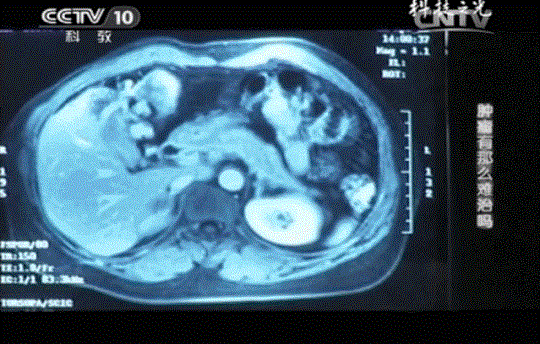

王女士的肝脏上出现了一个直径约为8cm的肝转移肿瘤。毫无征兆就出现的肝转移肿瘤让王女士彻底地绝望了。她立即决定放弃治疗,与家人一起走完人生最后的半年时间。

不仅如此,连续4个月的CT结果对比分析,肝转移瘤从8公分缩小到2.5公分,肿瘤标记物指标回归正常,这些都说明肿瘤正在被免疫细胞一点点消灭。